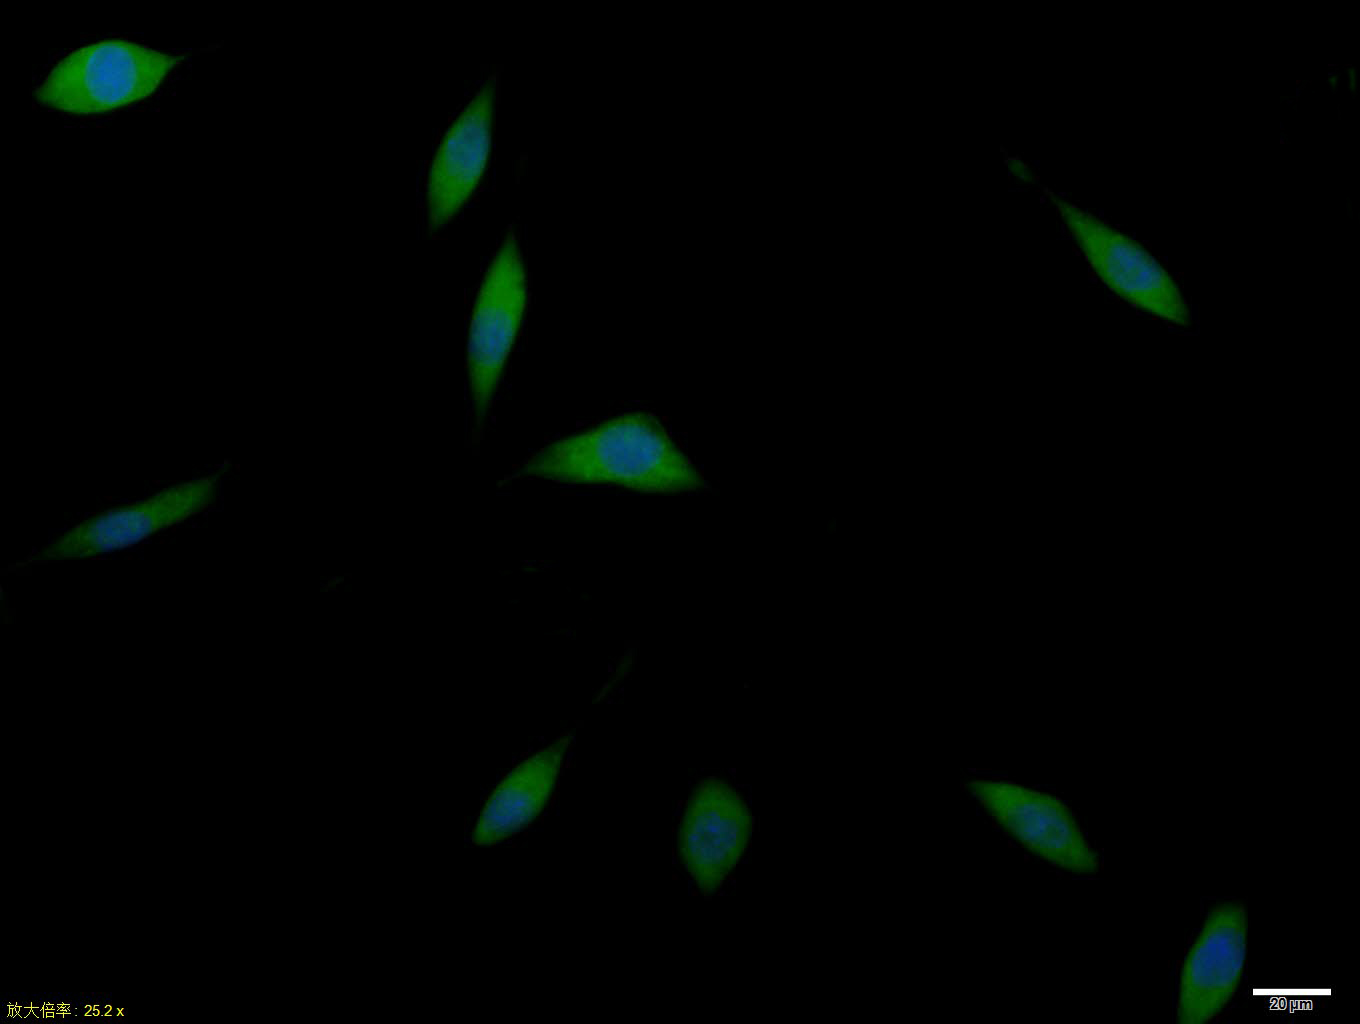

A-549 cell; 4% Paraformaldehyde-fixed; Triton X-100 at room temperature for 20 min; Blocking buffer (normal goat serum, C-0005) at 37°C for 20 min; Antibody incubation with (GLUT12) polyclonal Antibody, Unconjugated (bs-2540R) 1:100, 90 minutes at 37°C; followed by a conjugated Goat Anti-Rabbit IgG antibody at 37°C for 90 minutes, DAPI (blue, C02-04002) was used to stain the cell nuclei.

SHSY5Y cell; 4% Paraformaldehyde-fixed; Triton X-100 at room temperature for 20 min; Blocking buffer (normal goat serum, C-0005) at 37°C for 20 min; Antibody incubation with (GLUT12) polyclonal Antibody, Unconjugated (bs-2540R) 1:100, 90 minutes at 37°C; followed by a conjugated Goat Anti-Rabbit IgG antibody at 37°C for 90 minutes, DAPI (blue, C02-04002) was used to stain the cell nuclei.